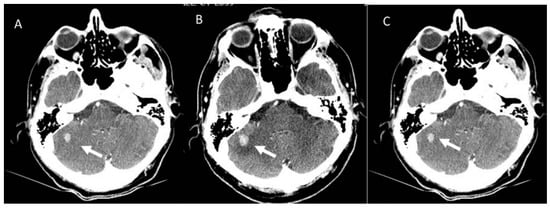

- Comstock, D.E.; Nishino, M.; Giardino, A.A. Headache in the setting of immunotherapy treatment for metastatic melanoma. JAMA Oncol. 2017, 3, 703–704. [Google Scholar] [CrossRef]

- Faje, A.T.; Sullivan, R.; Lawrence, D.; Tritos, N.A.; Fadden, R.; Klibanski, A.; Nachtigall, L. Ipilimumab-induced hypophysitis: A detailed longitudinal analysis in a large cohort of patients with metastatic melanoma. J. Clin. Endocrinol. Metab. 2014, 99, 4078–4085. [Google Scholar] [CrossRef]

- Min, L.; Hodi, F.S.; Giobbie-Hurder, A.; Ott, P.A.; Luke, J.J.; Donahue, H.; Davis, M.; Carroll, R.S.; Kaiser, U.B. Systemic high-dose corticosteroid treatment does not improve the outcome of ipilimumab-related hypophysitis: A retrospective cohort study. Clin. Cancer Res. 2015, 21, 749–755. [Google Scholar] [CrossRef]